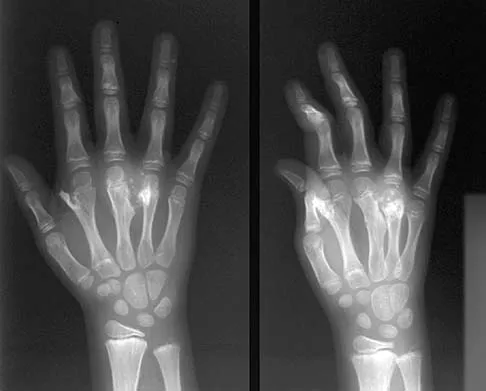

Figure 31 shows the AP and lateral radiographs of the elbow of a 56-year-old man with chronic polyarticular rheumatoid arthritis. His function continues to be limited by pain with activities of daily living. Examination shows that his total arc of motion is 110 degrees. Nonsurgical management has failed to provide relief. Treatment should now consist of

A semiconstrained prosthesis can provide excellent results in carefully selected patients. Because the radiographs show extensive joint destruction with loss of the capitellum and trochlea, a capitellocondylar total elbow (unconstrained) prosthesis is contraindicated. Elbow fusion is poorly accepted, and the radiographs show too much articular destruction for a radial head excision, synovectomy, or interposition arthroplasty to be effective. Ewald FC, Simmons ED Jr, Sullivan JA, et al: Capitellocondylar total elbow replacement in rheumatoid arthritis: Long-term results. J Bone Joint Surg Am 1993;75:498-507.